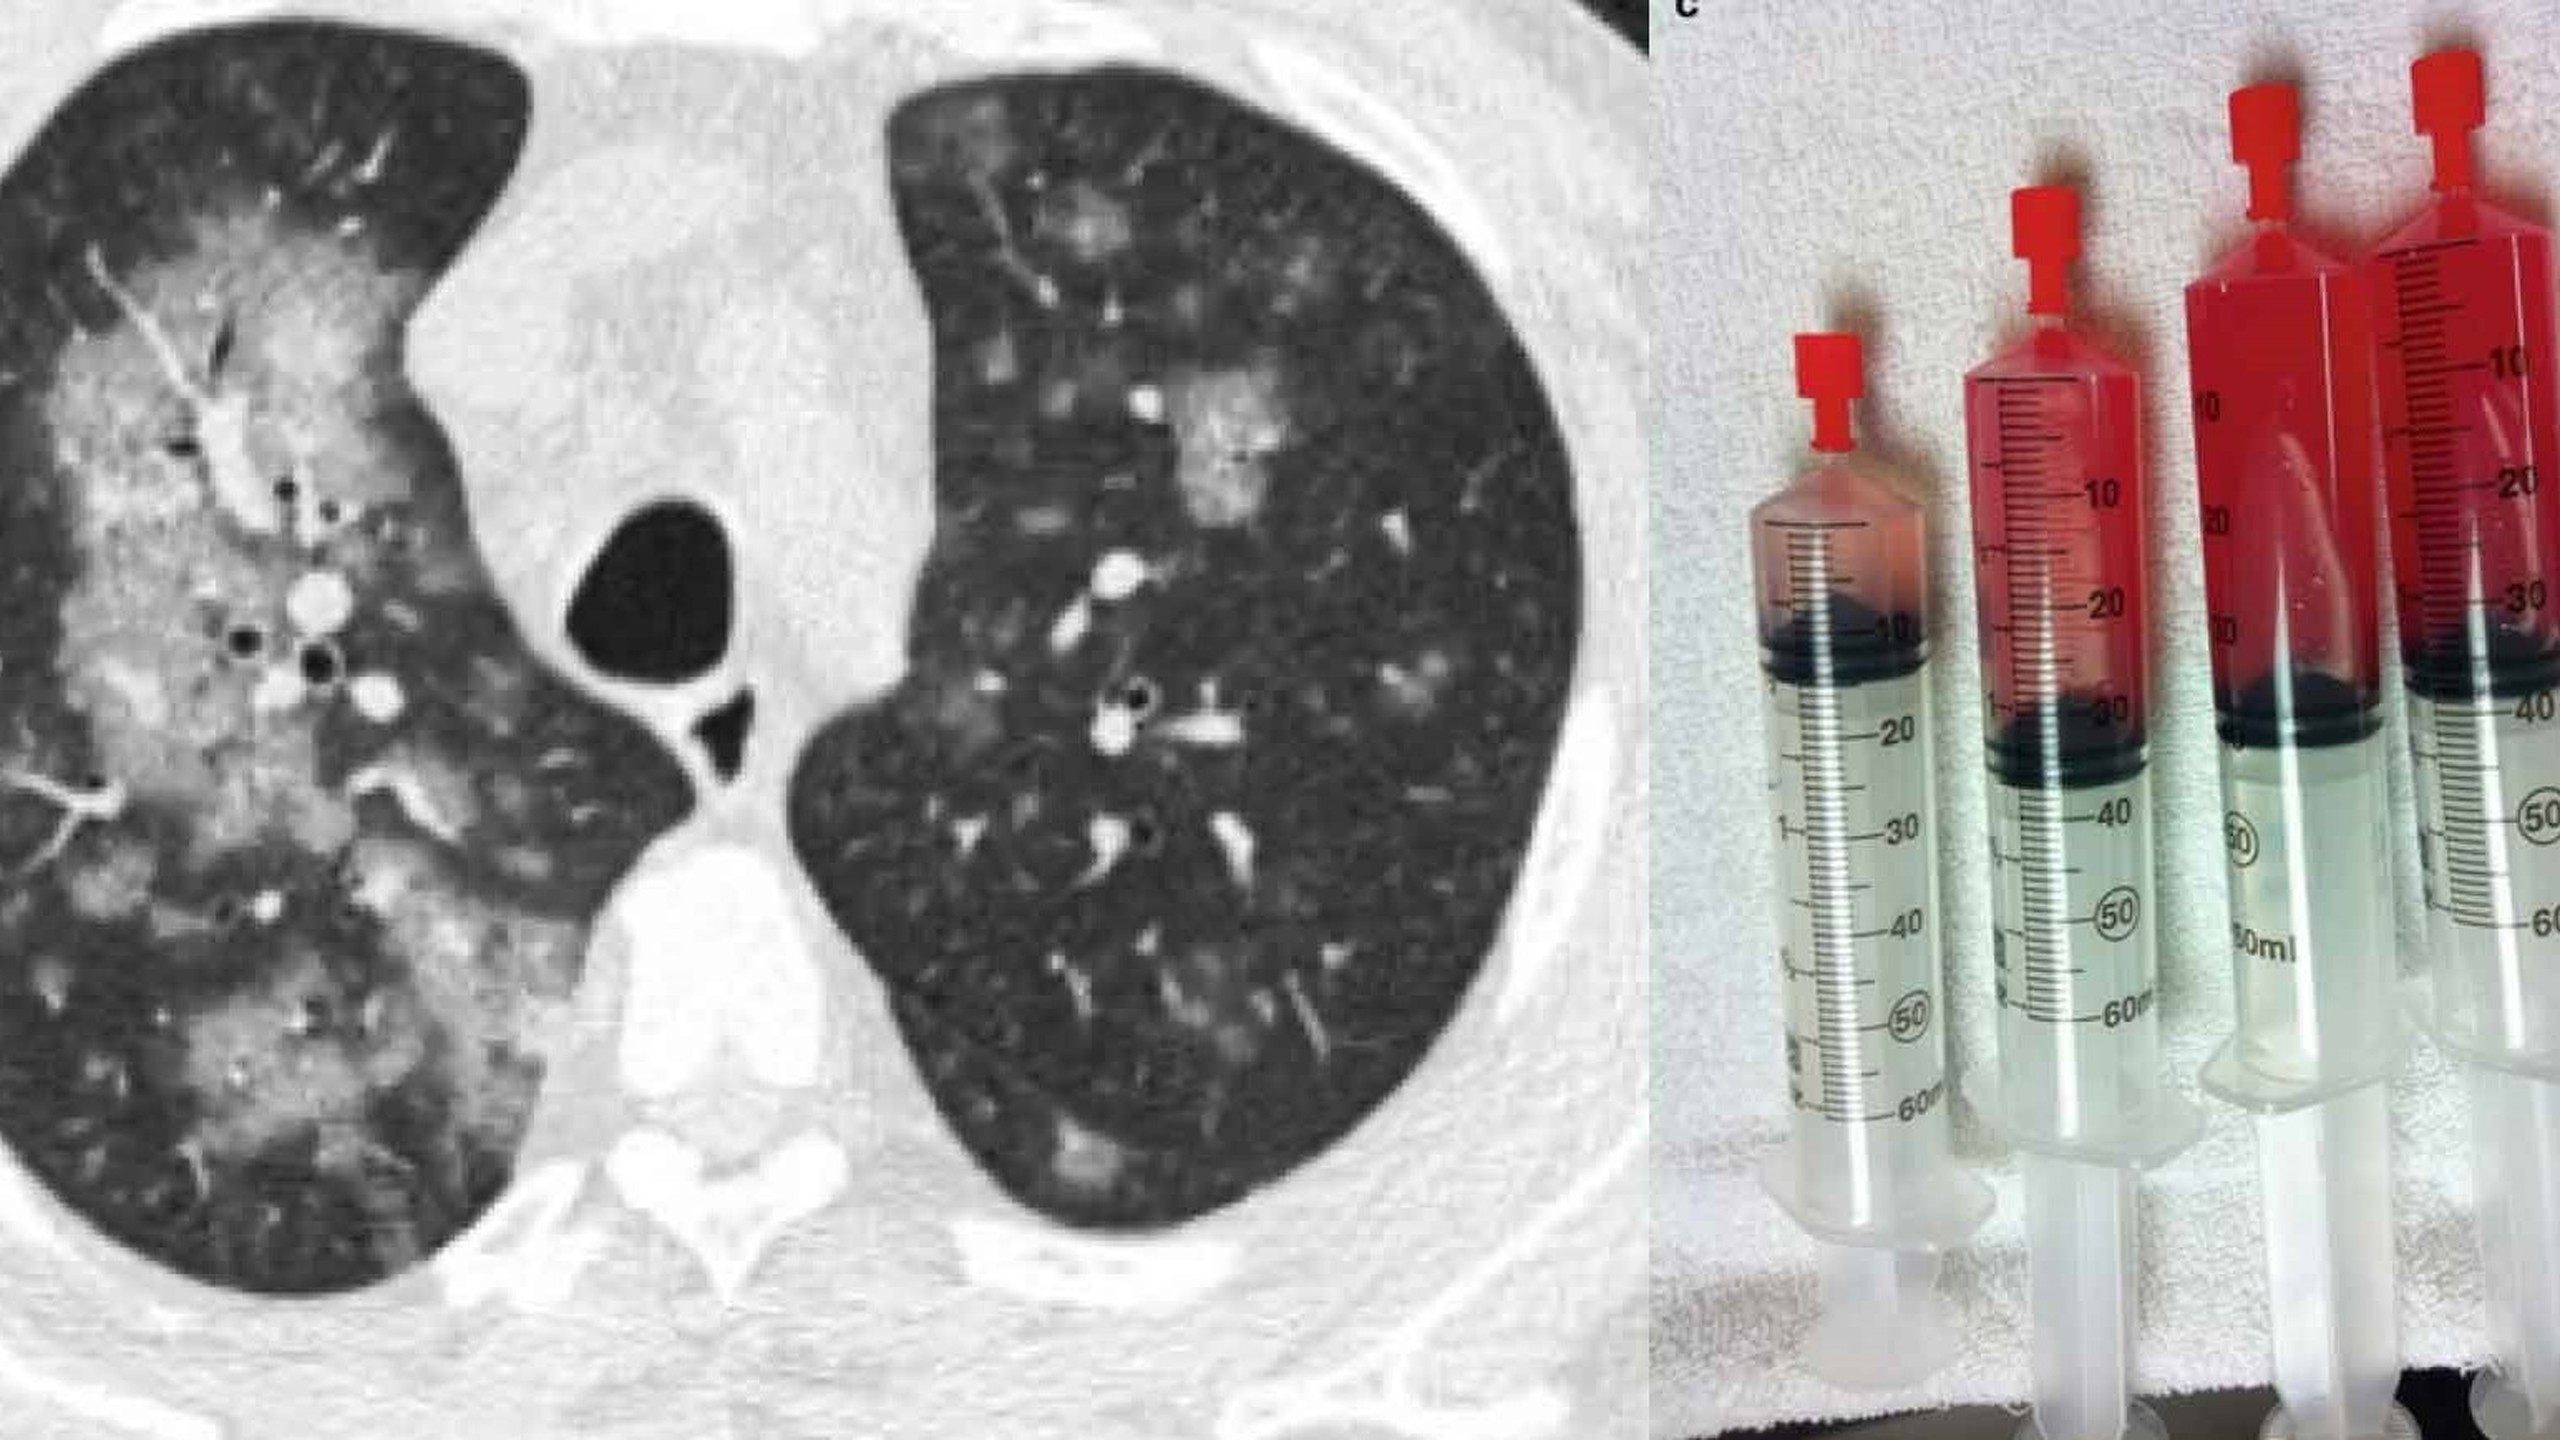

Triệu chứng lâm sàng của bệnh thường kín đáo ở giai đoạn đầu nên dễ bị bỏ sót. Trên thế giới đã có một số nghiên cứu về bệnh xuất huyết phế nang lan tỏa, đa số đều cho thấy có nhiều bệnh nhân bị chẩn đoán muộn. DAH là hội chứng tổn thương màng mao mạch - phế nang ở phổi, dẫn đến chảy máu từ mao mạch phổi vào trong phế nang. Các triệu chứng thường xuyên xuất hiện bao gồm:

Xuất huyết phế nang vô căn không chỉ gây lo lắng, mệt mỏi cho người mắc mà nó còn có các biến chứng nghiêm trọng ảnh hưởng đến khả năng hô hấp, chức năng phổi và tính mạng người mang bệnh. Chẩn đoán sớm và điều trị phù hợp có thể làm giảm tỷ lệ tử vong của bệnh. Về sinh lý bệnh, có 2 nguồn cấp máu chính cho phổi là tuần hoàn phế quản và tuần hoàn phổi. DAH là tình trạng chảy máu từ nguồn tuần hoàn phổi, là nguồn cấp máu áp lực thấp nhưng thể tích tuần hoàn cao, do vậy chảy máu thường có tính chất lan tỏa, ít gây ho máu nhưng bệnh nhân dễ suy hô hấp và thiếu máu nặng.